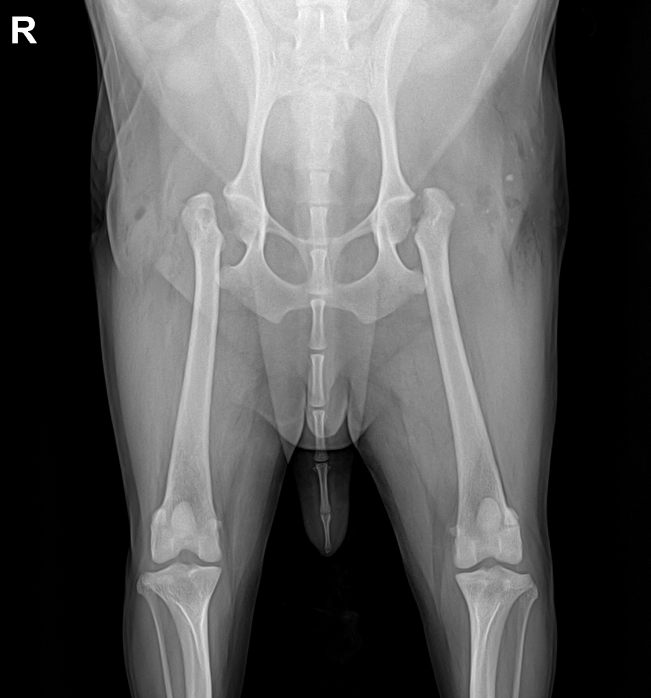

오늘 포스팅은 강아지가 갑자기 뒷다리에 힘이 안들어가요.반려견이 걷는 게 이상해요라는 주제로 시작할게요.

개 뒷다리 통증은 개의 고관절 이상견의 슬개골 탈구견 근육 손상 등의 다양한 이유가 있습니다.

그렇기 때문에 정확한 평가를 위해 강아지 방사선 촬영이 매우 중요합니다.

오늘 소개해드릴 아이는 동그라미에 표시된 엉덩이 관절, 즉 고관절 퇴행성 관절염 때문에 아이가 많이 아파했습니다.

학부모님과 상의 후 아이는 양쪽 고관절 수술을 시행하기로 하였습니다.